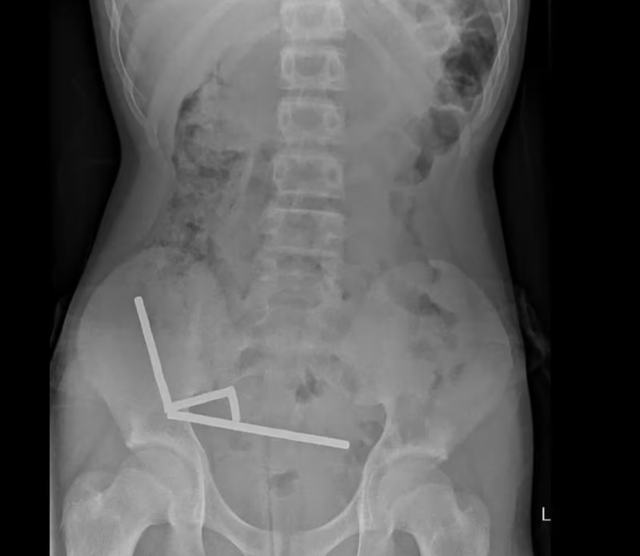

Khai tác tiền sử bệnh trước khi được đưa đến bệnh viện, cậu bé đã chịu đựng cơn đau bụng kéo dài bốn ngày. Tại đây, em cho biết đã nuốt số nam châm này khoảng một tuần trước đó. Kết quả chụp chiếu cho thấy chúng đã kết lại thành bốn chuỗi trong ổ bụng, kéo các đoạn ruột lại với nhau bằng lực từ. Hình ảnh bị nhiễu do từ tính mạnh buộc các bác sĩ phải tiến hành phẫu thuật khẩn cấp.

Những viên nam châm được lấy ra khỏi bụng cậu bé. Ảnh: Tạp chí Y khoa New Zealand.